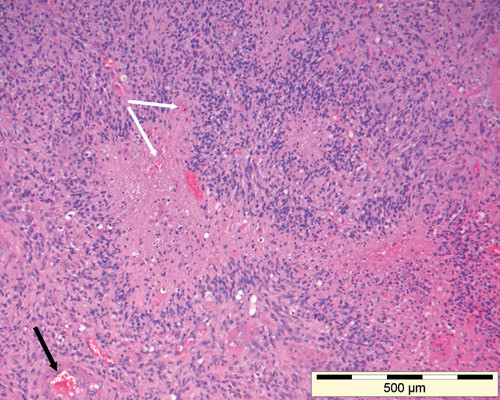

Radiologisk diagnose er likevel beheftet med usikkerhet, og histologisk diagnose er derfor sentralt (3). Dersom beliggenhet eller pasientens tilstand forhindrer reseksjon av svulsten, bør man likevel tilstrebe å få tatt en biopsi. Frysesnitt fra svulsten kan vurderes peroperativt. Diagnosen sikres ved å mikroskopere fiksert vev som er innstøpt i parafin, skåret i tynne snitt og farget med histokjemiske og immunhistokjemiske metoder. Patologen må vurdere om biopsimaterialet er representativt, reaktivt eller neoplastisk, og om det dreier seg om en primær hjernesvulst eller en metastase (fig 2). Primære hjernesvulster klassifiseres etter histogenese (astrocytt-, oligodendroglia- eller ependymderivert svulst) og graderes i prognostisk øyemed etter WHO-klassifiseringssystemet (4). I dette systemet klassifiseres høygradige gliomer som grad III-IV.